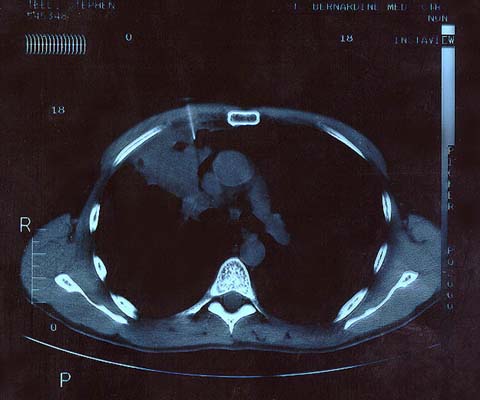

Scan 25th March 1999 No2